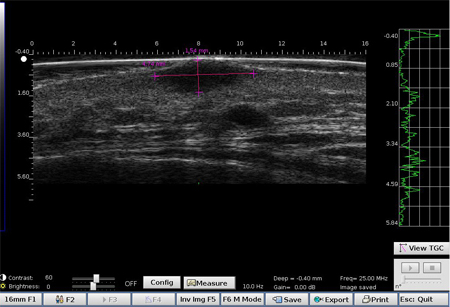

Mélanome ulcéré sur l’avant bras (épaisseur mesurée à 3.68 mm à l’échographie, épaisseur histologique).

Lésion infiltrant le derme.